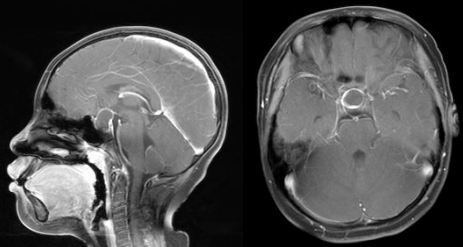

患者因甲状腺功能减退在当地医院完善颅脑MRI发现垂体病变,前来我院就诊,影像学检查显示鞍区存在占位性病变。鞍区位置深在,解剖结构复杂,周围密布重要神经血管,传统开颅手术创伤大、风险高。为最大程度保护患者神经功能、减少创伤,科室经过严谨的术前讨论,决定为其实施目前国内前沿的“神经内镜下经鼻蝶入路微创手术”。

术前MRI影像